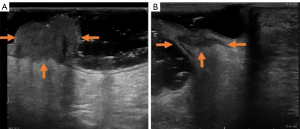

3D-ERUS was conducted 1 week before CRT (3D-ERUS1) and before surgery (6–8 weeks after completion of CRT, 3D-ERUS2) with a Pro Focus 2202 scanner (BK, Denmark) equipped with a three-dimensional (3D) endorectal probe 8838 or 2502 (6–16 MHz, BK, Denmark). The patient was placed in the left lateral decubitus position, then 50 mL gel was injected into the rectum and anal canal to expand the rectal lumen. The probe was inserted through rectum and anal canal, and advanced above the lesion of interest in order to evaluate the entire lesion comprehensively. After initial observation of the tumor, 3D volume images were obtained in all patients before and after CRT treatment by using automatic rotating imaging of sampling function, and the data was stored on the machine. 3D-ERUS volumetry measurements were performed on 3D Viewer (version 5.19, BK, Denmark) by an independent sonographer with 3 years’ experience in 3D-ERUS who was blinded to the pathology results. The lesion boundaries on the 3D-ERUS image were manually traced by the sonographer on every transverse‑sectional tumor area by a slice section thickness of 2 mm (Figure 1). After multiplying every transverse-sectional tumor area, the total volumes of the tumor were automatically calculated. The tumor volume measured pre-CRT was recorded as Vpre-CRT, whereas the tumor volume measured post-CRT was recorded as Vpost-CRT. Finally, the TVRR was calculated as TVRR = (Vpre-CRT − Vpost-CRT)/Vpre-CRT × 100% (17).